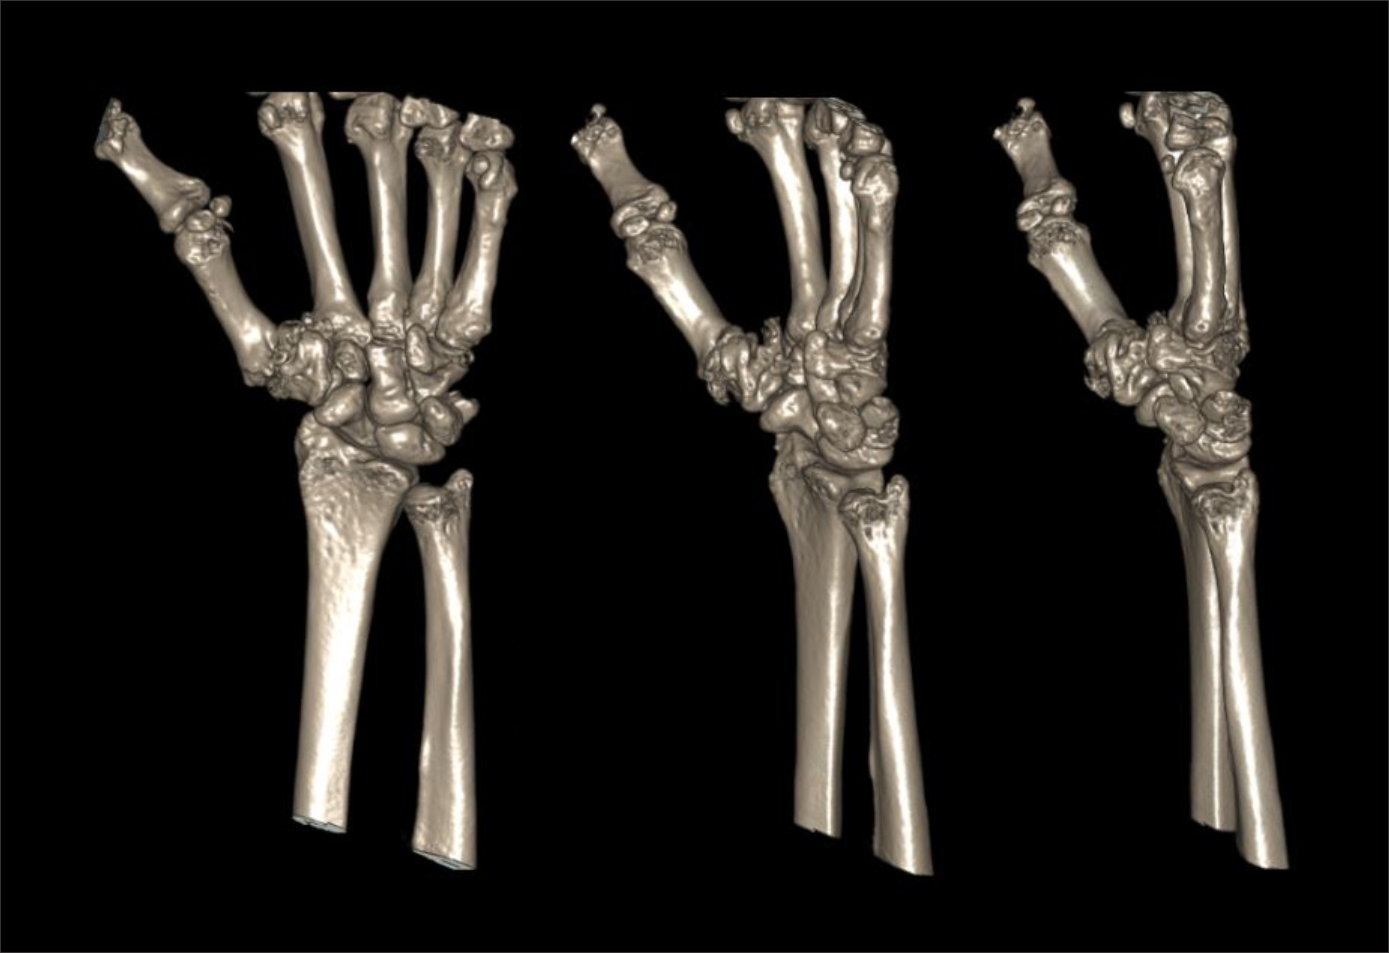

- Coronal, sagittal and axial images in both soft tissue (WW:500, WL:50) and bone (WW: 3500, WL: 350) window with ≤2mm slice thickness.

- 3d images to show pathologies clearly.